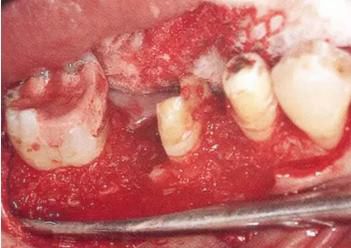

▲圖11-3,4

▲圖11-3,4 齦瓣剝離翻開(kāi)的狀態(tài)。右下6的遠(yuǎn)中牙根有較深的骨組織缺失,右下7的頰側(cè)有II度根分叉病變和近遠(yuǎn)中側(cè)有垂直型骨組織缺失。

360截圖20170422102040585.jpg

▲圖11-5

右下6進(jìn)行牙半切除并將遠(yuǎn)中牙根拔除。右下5,7的骨組織缺損部位進(jìn)行骨組織移植,以及在右下7進(jìn)行GTR(wraparound)。